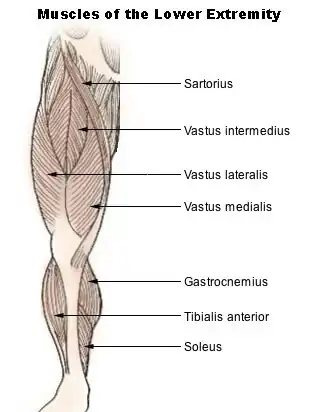

Мышцы нижней части конечности | |

Четырёхгла́вая мы́шца бедра́ (квадри́цепс, лат. musculus quadriceps femoris) занимает всю переднюю и отчасти боковую поверхность бедра. Состоит из четырёх головок.

Медиальная широкая мышца бедра

Медиальная широкая мышца бедра (musculus vastus medialis) занимает переднемедиальную поверхность нижней половины бедра. Мышца берёт начало от медиальной губы шероховатой линии бедренной кости и, направляясь вниз, переходит в широкое сухожилие, которое частично вплетается в широкое сухожилие вместе с прямой мышцей бедра, а частично прикрепляется к медиальному краю надколенника, образуя медиальную поддерживающую связку надколенника. Таким образом образующие мышцу пучки направлены косо сверху вниз и изнутри наперёд[1].

Латеральная широкая мышца бедра

Латеральная широкая мышца бедра (musculus vastus lateralis) занимает почти всю переднелатеральную поверхность бедра. Сверху она несколько прикрыта мышцей, напрягающей широкую фасцию, а спереди — прямой мышцей бедра. Мышца начинается от большого вертела, межвертельной линии и латеральной губы шероховатой линии бедра. Направляясь вниз, мышца переходит в широкое сухожилие, которое входит в состав общего сухожилия четырёхглавой мышцы и участвует в образовании латеральной поддерживающей связки надколенника[1].

Промежуточная широкая мышца бедра

Промежуточная широкая мышца бедра (musculus vastus intermedius) располагается на передней поверхности бедра между медиальной и латеральной широкими мышцами бедра, непосредственно под прямой мышцей бедра. Является наиболее слабой среди остальных головок. Начинается на передней поверхности бедренной кости — от межвертельной линии и, направляясь вниз, переходит (почти на половине своей длины) в широкое сухожилие, которое в дистальном отделе присоединяется к сухожилию прямой мышцы бедра, переходя в общее сухожилие четырёхглавой мышцы[1].